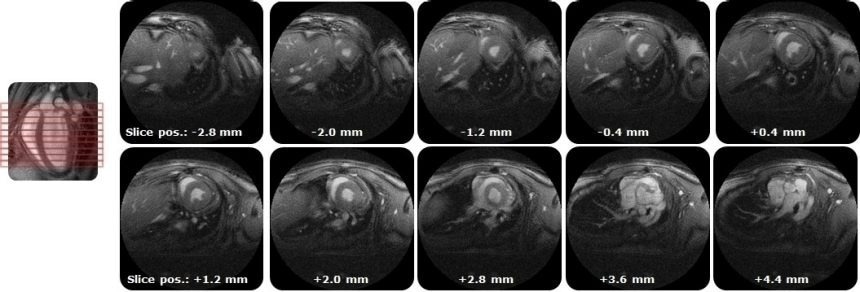

IntraGateUTE, with its radial readout, enables high-quality cardiac cine data in shortest measurement time. Image Credit: Bruker BioSpin Group